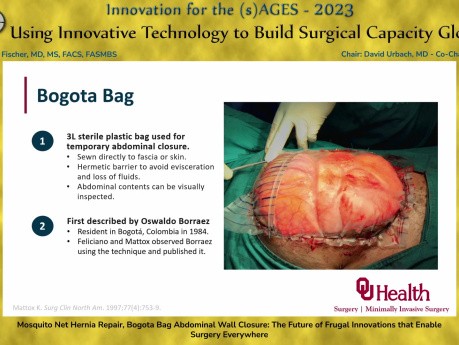

Reparación de hernia con mosquitero, cierre de...

Esta charla fue presentada en la sesión Uso de tecnología innovadora para desarrollar capacidad quirúrgica a nivel mundial por Laura Fischer MD, MS, FACS, FASMBS el 30 de marzo de 2023 durante la Reunión...